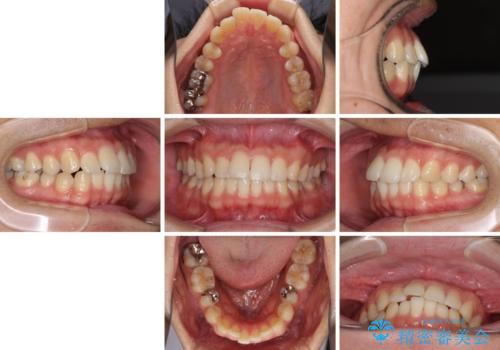

- 矯正治療の後戻りを気にして来院された患者様です。

後戻りは軽微でしたので、インビザライン・ライトにより矯正治療を行うこととしました。